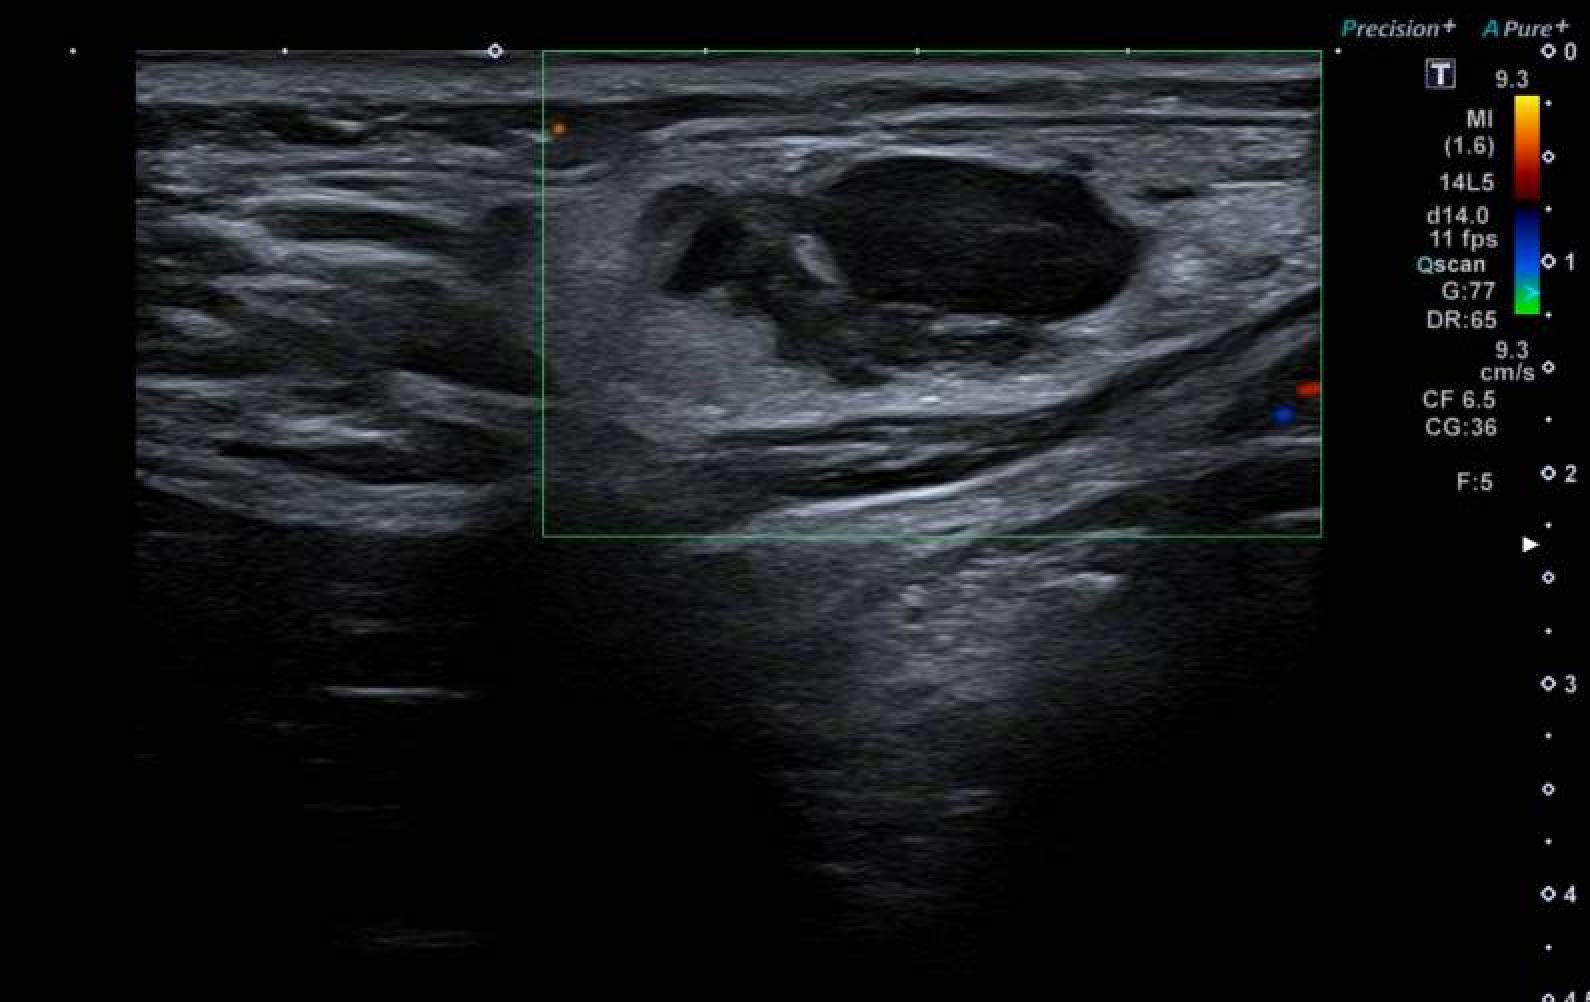

AP: Hombre, 25 años, no RAM, fumador de 10 cigarrillos/día. Antecedente de sífilis tratada. Alergia a ácaros. Convivencia con cuatro gatos. Tratamiento habitual: antihistamínicos a demanda.Hallazgos ecográficos

Se identifica una adenopatía supraclavicular derecha de morfología polilobulada, pérdida del hilio graso, hipervascularización interna y tamaño de 22 × 11 mm, hallazgos claramente patológicos, con pequeños ganglios adyacentes y sin adenopatías laterocervicales significativas.Pruebas complementarias